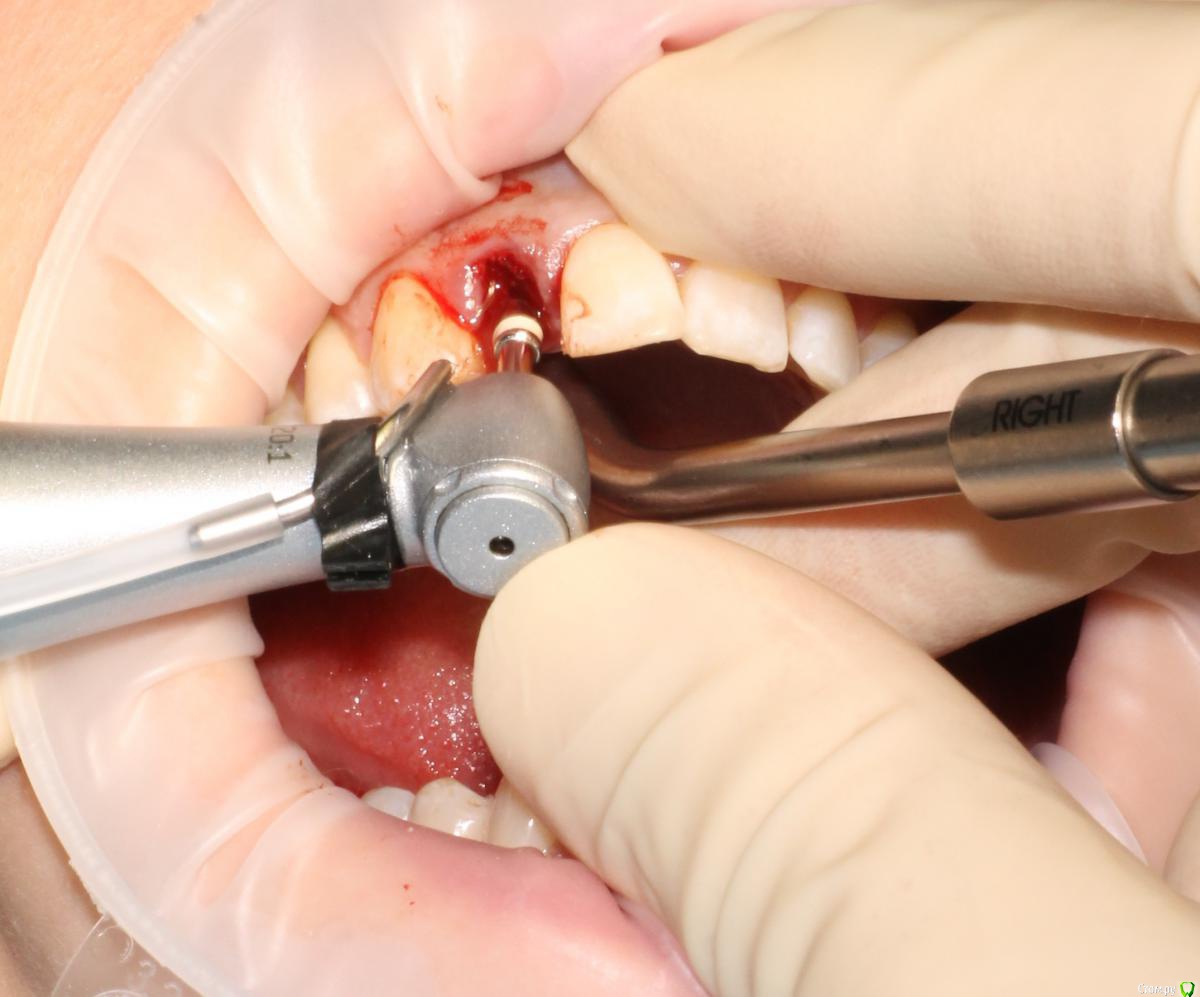

MenshikovDV Опубликовано 2 апреля, 2015 Поделиться Опубликовано 2 апреля, 2015 (изменено) Зуб 1.2 отлом коронковой части зуба, на период ожидания приема у хирурга и ортопеда (2 дня) приклеен к соседям. Вся процедура в одно посещение. Где-то часа два. Я ортопед, хирургия не моя, фото мои Изменено 2 апреля, 2015 пользователем MenshikovDV 19 Ссылка на комментарий